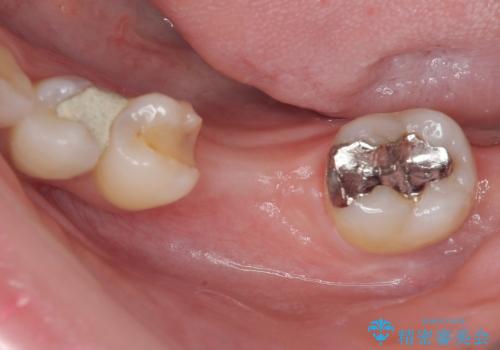

- ブリッジの歯のないところにインプラントを入れて、銀歯を白くやり替えたいと来院された患者様です。

歯の欠損している箇所にはインプラント治療をし、銀歯と仮詰めの部分はセラミックインレーにて補綴することとしました。